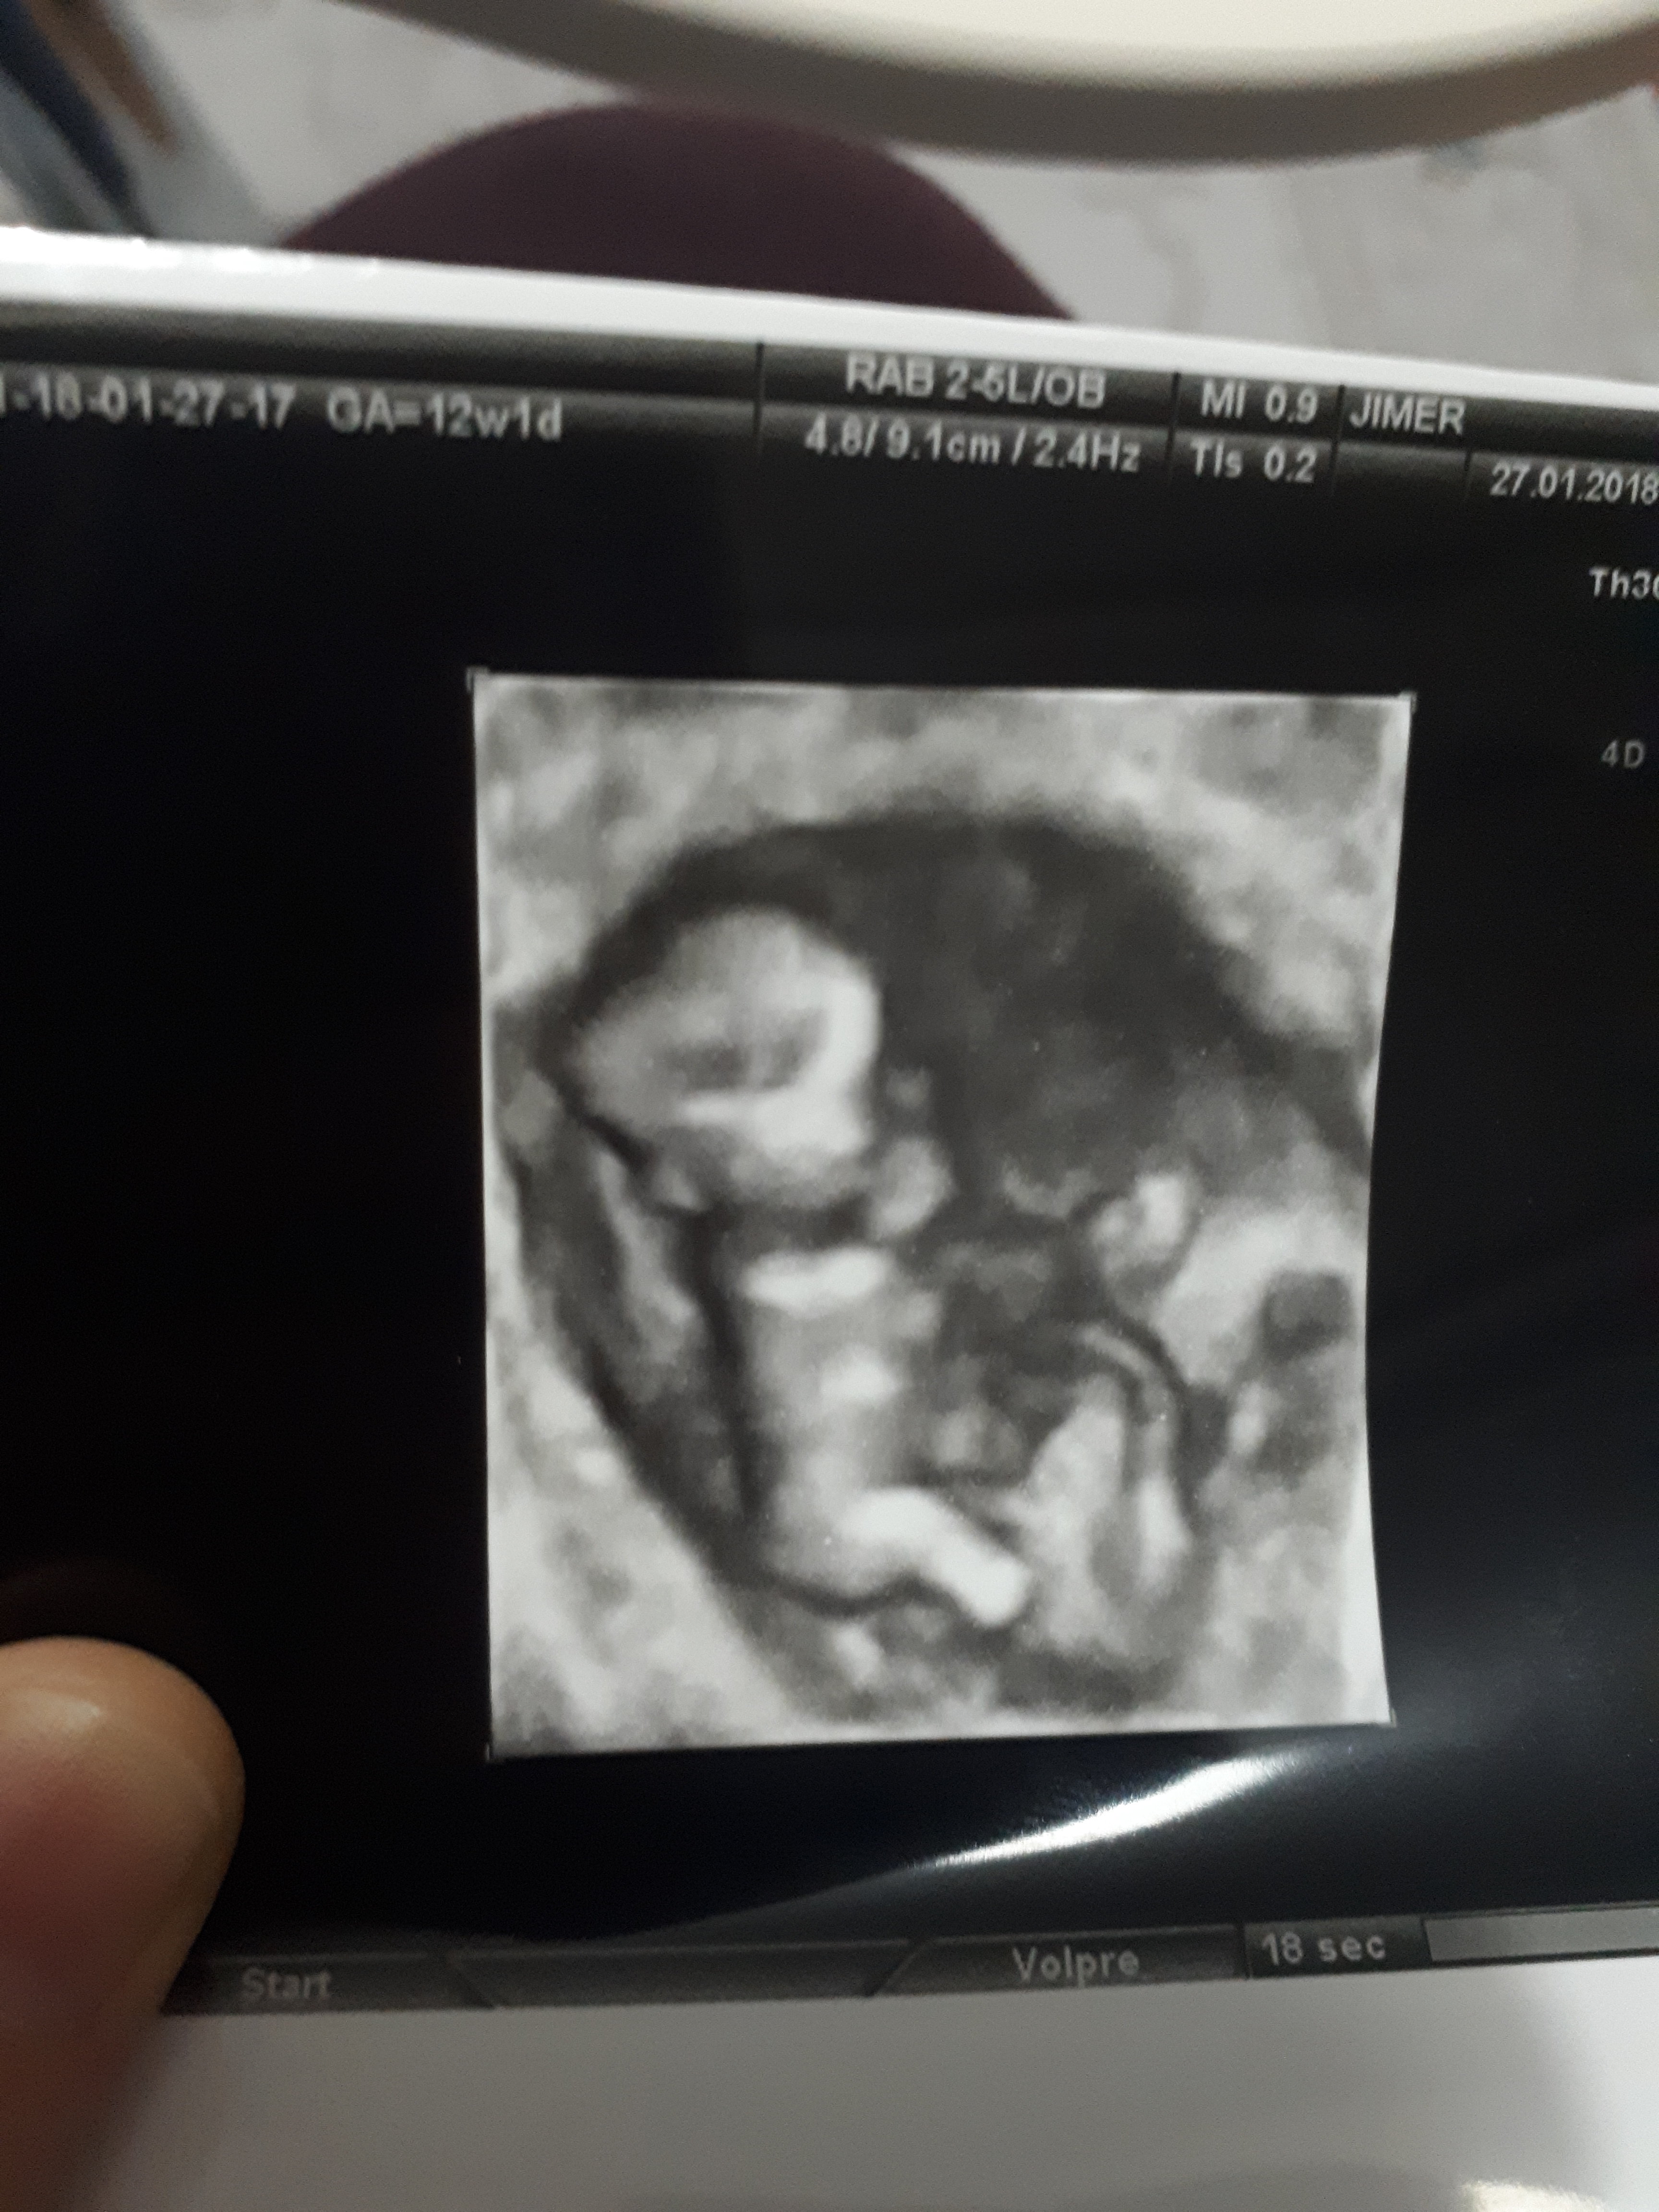

Hadi darısı bana insallah hayırlı olsunbenim nub teorisi doğru çıktı bebeğim kız 🙂

Birde şu görüntü var bunda peki bellimi ama burada 11 haftalikMerhaba canım bebeğinin pozisyonundan dolayı nub çıkıntısı görünmüyorki

Teşekkür ederim🙂Zaten şöyle söylim bu haftalarda yanılma payı çok yüksek bebeğin cinsiyetini yirminci haftalara yakın net olarak öğrenebilirsiniz . Allah hayırlısını versin inş.